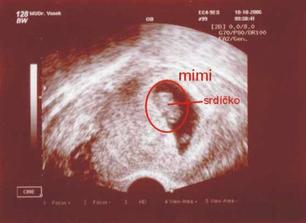

Po návratu z dovolené jsme shodou okolností byli hosté na 3 různých svatbách po sobě jdoucích, bylo to období radosti a veselosti, přesně jako svatby jsou....a v tomto období se nám s manželem podařilo počít naše miminko, přičemž, když jsme to 13.9. zjistili (shodou okolností měli moji rodiče výročí svatby), nevěřili jsme tomu....vždyť nás čekalo už umělé oplodnění a my jsme to nakonec zvládli sami!!!

Nedovedete si představit to velké štěstí...které nás potkalo, je to prostě náš ZÁZRAK. Teď jsem sice plná obav a strachu o miminko, i nějaké komplikace se vyskytli, ale snad všechno dobře dopadne, a nám se v květnu, rok po naší svatbě, narodí krásné a zdravé miminko...náš malý - Velký Zázrak.